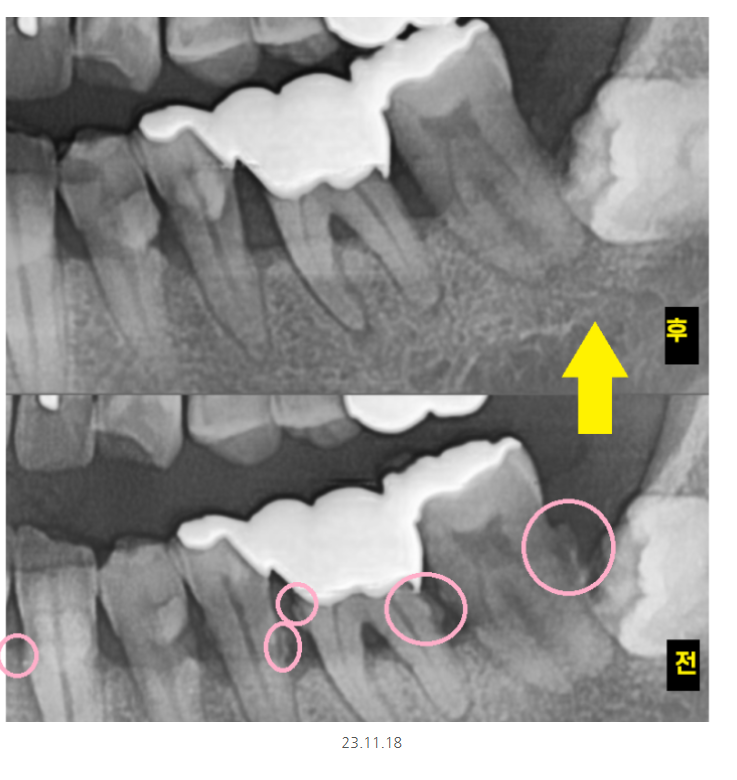

전반적으로 잇몸이 많이 내려가신 상황이었는데요.

불편을 호소하신 오른쪽 치아를 보니

겉으로 보기에는 닳은 치아가 있긴 했지만

환자분 연령을 생각하면 크게 문제가 되는것은 아니었습니다.

잇몸뼈가 많이 내려가

치아를 움직여봤는데요.

어금니가 들썩 들썩

위 아래, 좌우로 움직였습니다.

치아가 뽑힐정도로 말이죠.

어금니 시림의 원인 치아가 파여서

충치가 있어서

잇몸이 안좋아서

다양한 원인이 있지만

해당 환자분은 잇몸이 안좋아서

이가 시리신거였습니다.

x-ray상에서 치석이 보일정도로

치석도 많고 잇몸관리가 안되고 계셨어요.

오른쪽 어금니 시림으로 내원하셨지만

다른 치아들도 상태가 영 .. 좋지 않았죠.

제일 불편을 호소한 치아 한개만 발치 후

임플란트를 진행했습니다.